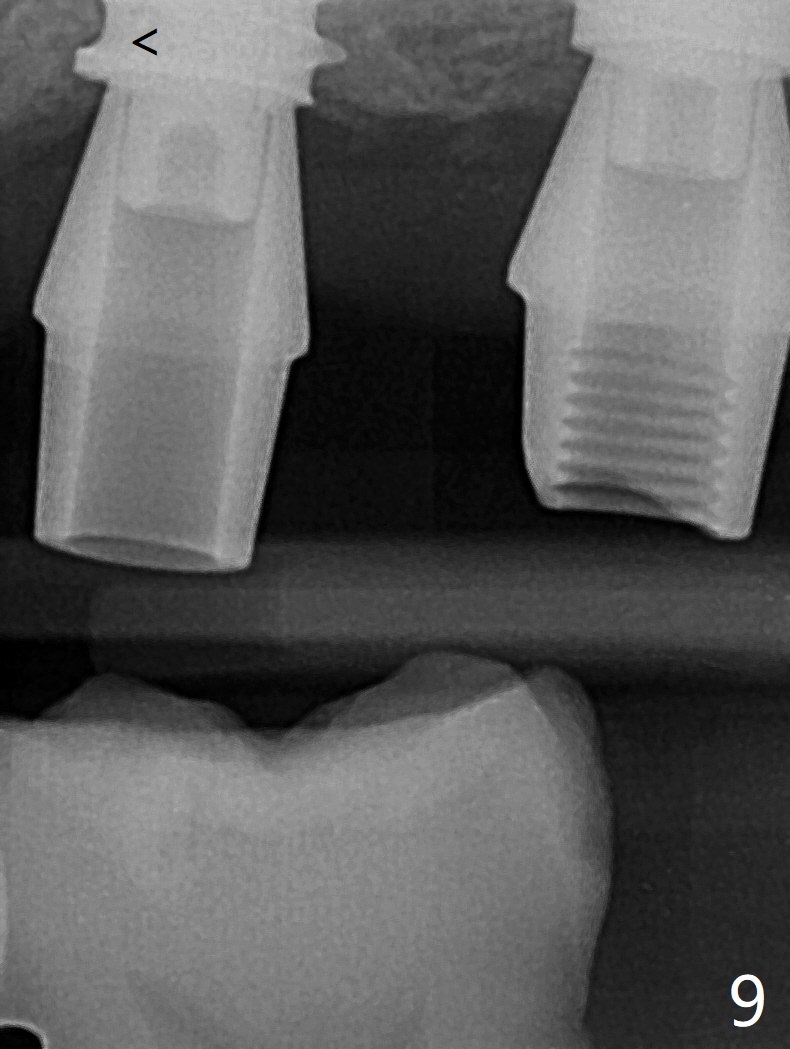

After finishing osteotomy with IS guide and Tatum Tapered tap 5x14 mm for 11 mm (gingival level) free hand, a 5x11 mm Tatum implant is placed at #18 with >15 Ncm (Fig.1). Bone harvested from the site of #18 will be used for #15 sinus lift (Fig.2 * as well as allograft). By the similar fashion, osteotomy at #15 is finished according to IS drill sequence except underdrilling (4.0x7.3 mm drill with 2 O-rings). Following use of DIO Sinus Approach Kit and placement of 2 pieces of PRF membrane and mixture of autogenous and allograft for sinus lift, a 4.5x11 mm IBS dummy implant is placed (Fig.2). With more allograft for sinus lift, a 5x9 mm implant is inserted with >35 Ncm (Fig.3). At #18 the implant 2.5 months postop (Fig.4) seems ok with removal of the cover screw and placement of a healing cuff. The implant at #15 appears osteointegrated with sinus lift 2.5 months postop (Fig.5 *). Half month later, the implant at #18 is tender associated with unipost placement. The healing abutment returns. A pair abutment (5.5x4(4) mm; 25 Ncm) is placed at #15. When the patient returns 7 months postop, BWs are taken to confirm that the abutment at #15 is fully seated, whereas that at #14 is not (Fig.6). A healing abutment is then placed at #14. Osteointegration seems to occur at #18; there is no tenderness when a 4.5x3 mm abutment is placed (Fig.7). Provisional crowns are fabricated at #15 and 18 for progressive loading. When the patient returns 14 months postop, a 5x4(4) mm hex abutment is placed at #14 with apparent gap between the implant and abutment (Fig.8 (PA) open arrow). In fact the gap seems to be absent more coronally as shown by bitewings (Fig.9,10 <). All of the 3 crowns are cemented in situ (Fig.11, 12) although the one at #14 is removed with the abutment for removal of residual cement. When the latter is re-torqued, the abutment remains completely seated (Fig.12). However, the implants at #15 and 18 appear to be placed distally with free-end guides (black lines).